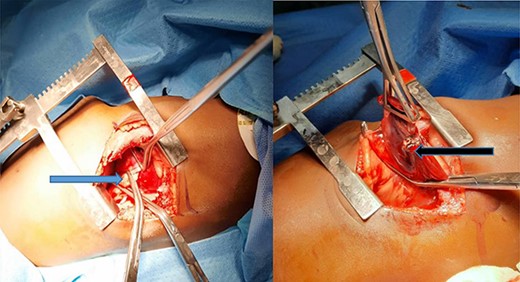

At surgery, the aberrant artery from the descending thoracic aorta (Fig. 3A) was dissected, isolated and doubly ligated with silk 1 and clips. A wedged resection of the sequestrated lung (Fig. 3B) was done, with Fig. 4 showing the normal lung after resection. No gastrointestinal tract communication was identified. A size 18F chest tube was left in situ after hemostasis. Patient was extubated on table and spent 2 days in the intensive care unit before being step down to the ward. The chest tube was removed on post-operative day 2 and he was discharged home on post-operative day 4 with subsequent follow-up on out-patient basis. He has been well with no complaints 6 months after surgery. Histopathologic evaluation of the resected sequestrated lung reported of thick-walled blood vessels in the lung parenchyma as well as evidence of hemorrhage and chronic inflammation within the alveolar spaces consistent with intralobar pulmonary sequestration.

(A) Blue arrow showing the anomalous artery from the descending thoracic aorta; (B) black arrow showing the erythematous and dense sequestrated lung.